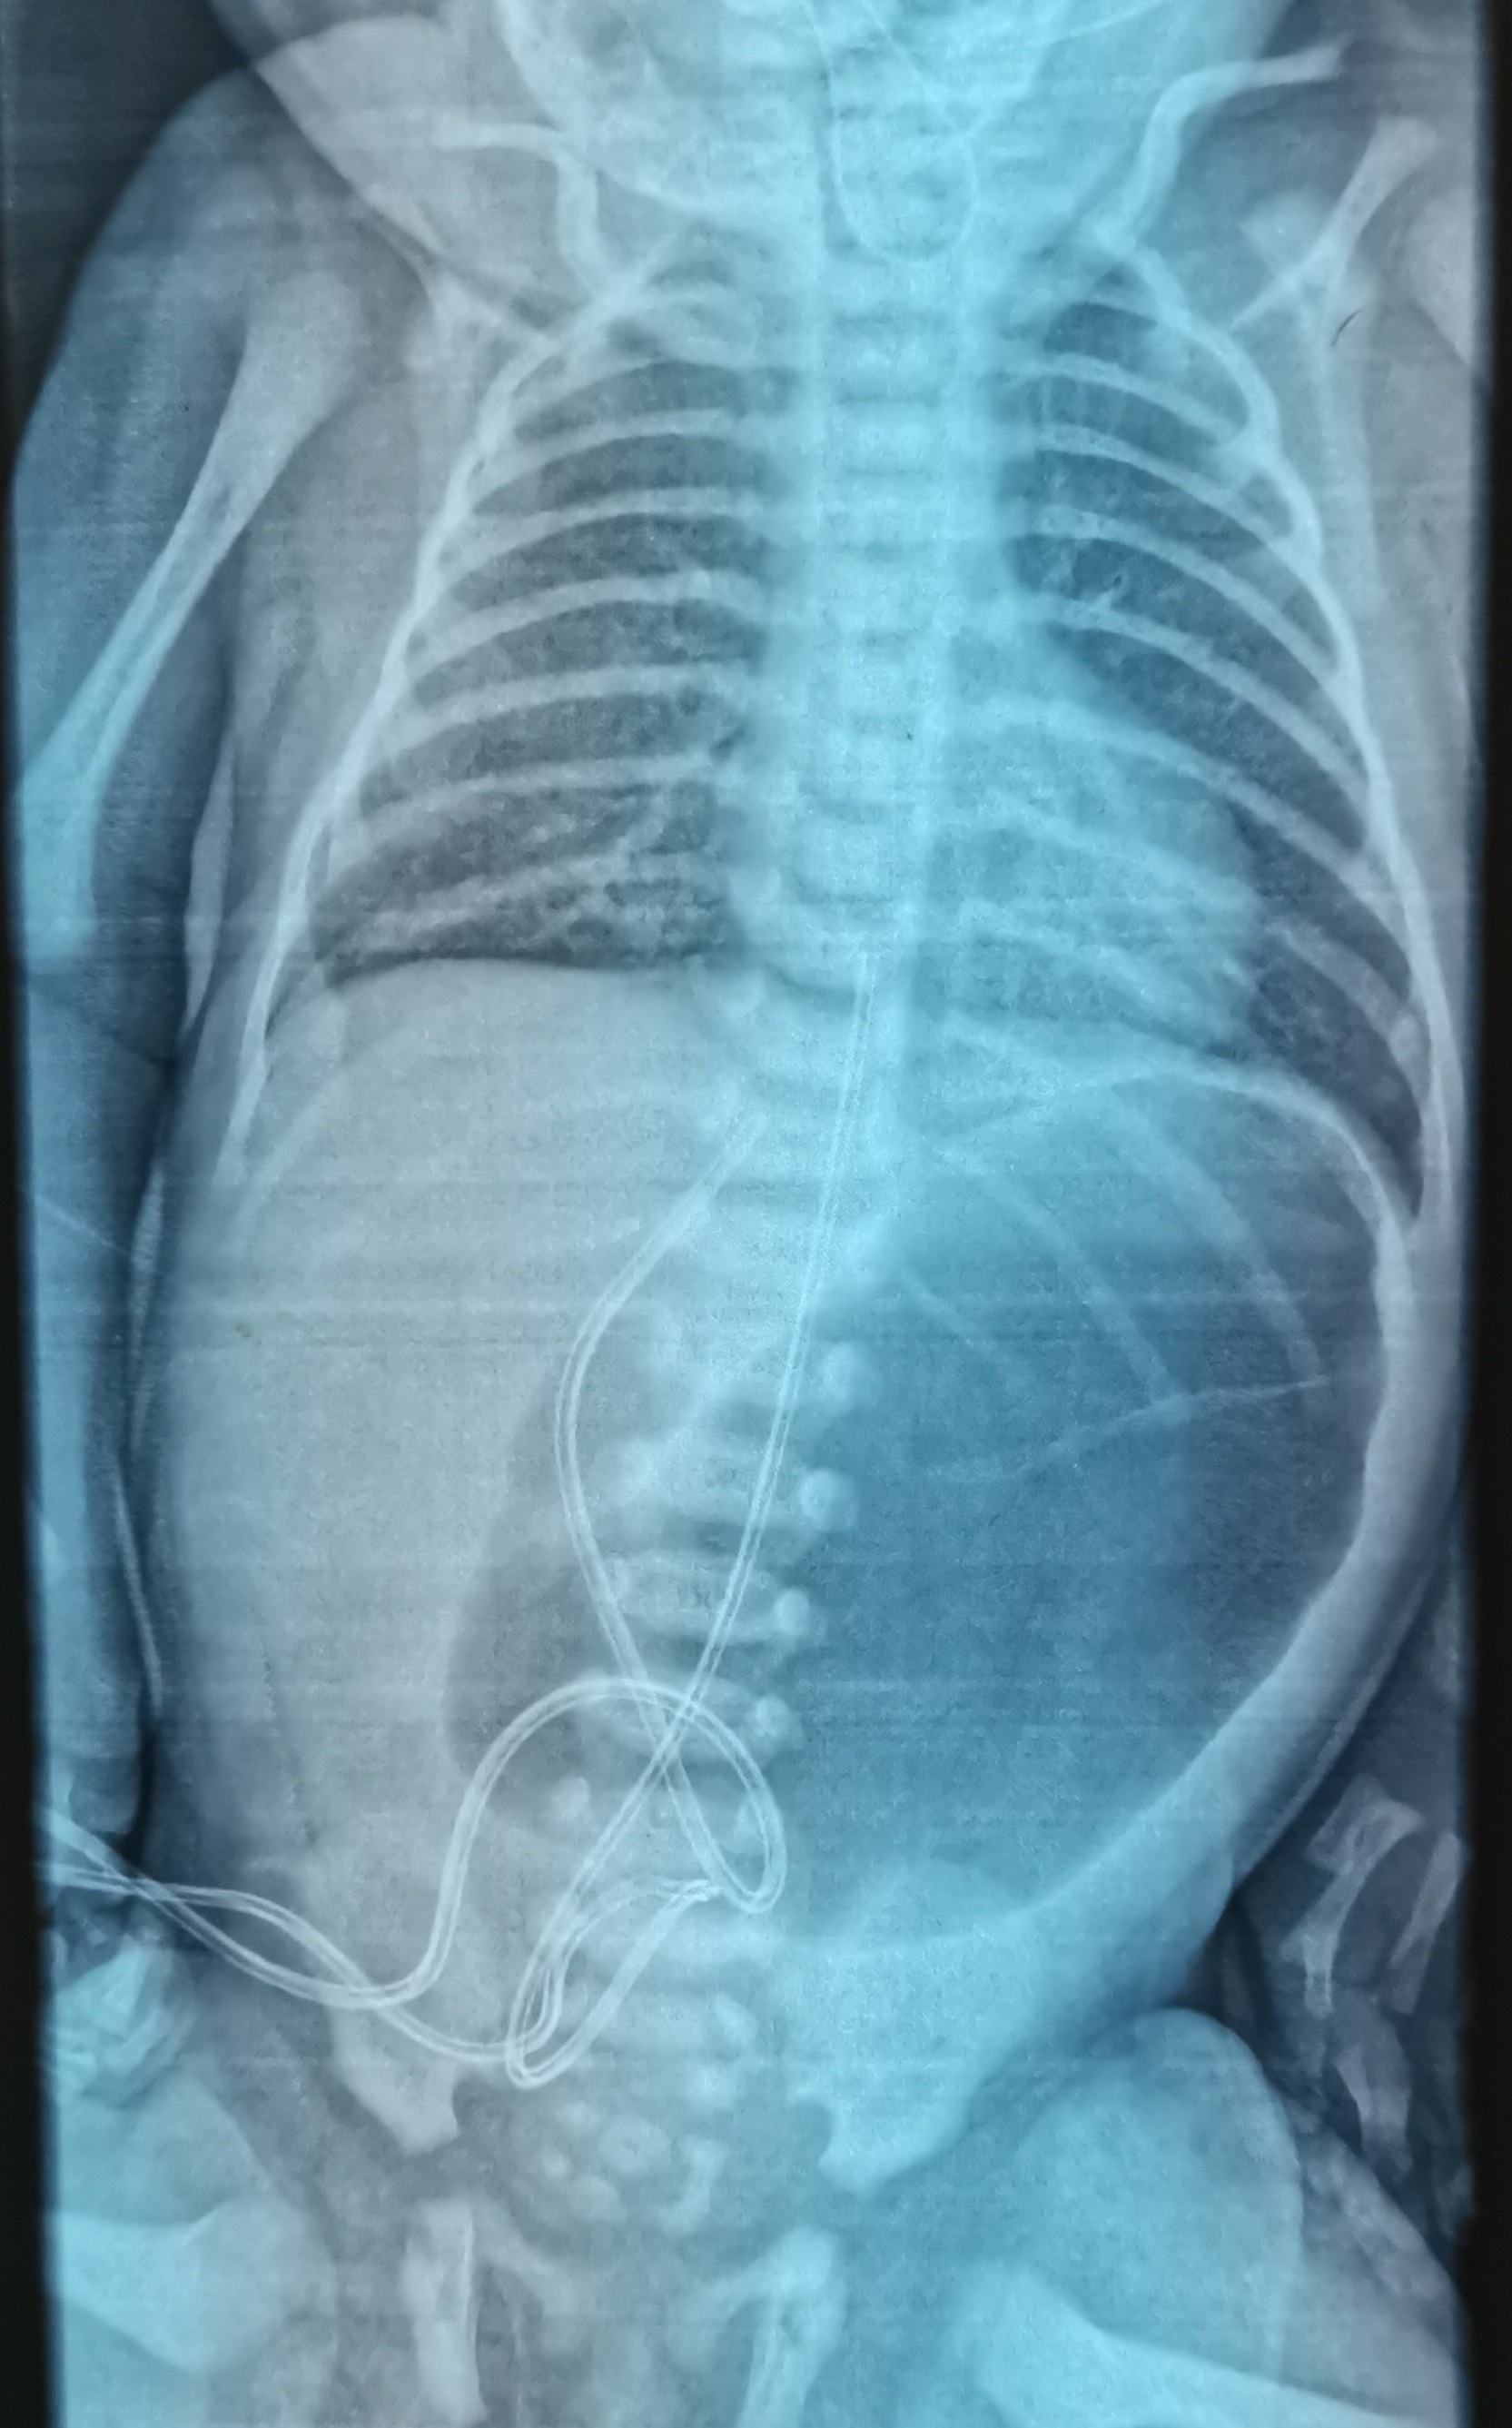

A term female neonate with a birth weight of 2.36 kg was referred to us for excessive drooling of saliva. Clinically the baby had no dysmorphism with unremarkable abdominal findings, and normal female genitalia but absent anal opening. Resistance was noted during Ryle’s tube insertion. Infantogram revealed coiling of Ryle's tube at T2-3 vertebra level, prominent gastric bubble, and duodenal cap with no distal bowel gas (Fig. 1). These findings made a provisional diagnosis of Type C esophageal atresia with distal tracheoesophageal fistula, duodenal atresia, and high-type anorectal malformation. Staged surgery began with right thoracotomy on day 3 of life through 4th intercostal space, with an extrapleural approach the fistula was ligated with prolene 5-0, and primary esophageal anastomosis completed using PDS 6-0. Postoperatively, the baby was shifted to NICU, ventilated on low settings, and hemodynamically supported with single inotropes.

Figure 1

Infantogram showing Coiling of NG tube in the upper thorax and dilated stomach and duodenal cap with no distal gas.